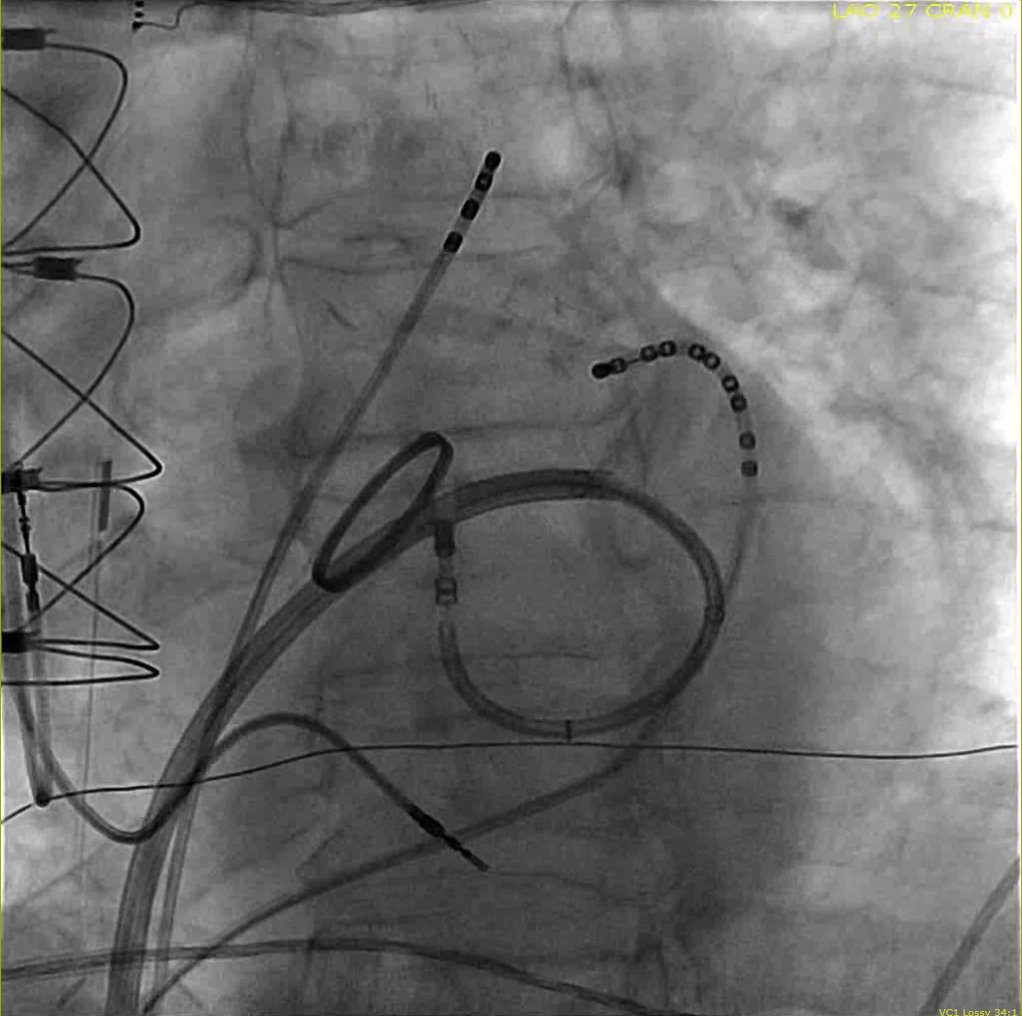

@annavarr @ReddyEPS @DrGregMichaud @jaymontgomery44 @ValayParikhMD I usually put a ring towards the entrance to the CS osmium to block the muscle sleeves extending from CS. Then I map connections from LA into the PLSVC and ablate in PLSVC until electrically silent with entrance and exit block.

@SethHSheldon @ReddyEPS @DrGregMichaud @jaymontgomery44 @ValayParikhMD I usually do a proximal and distal ring ablation

Patient with persistent AF and 3 prior AF ablations at an outside center. Congenital absence of the right SVC with massive PLSVC -- no prior ablation in the PLSVC. #EPPeeps What is your approach to ablation of PLSVC? @ReddyEPS @DrGregMichaud @jaymontgomery44 @ValayParikhMD